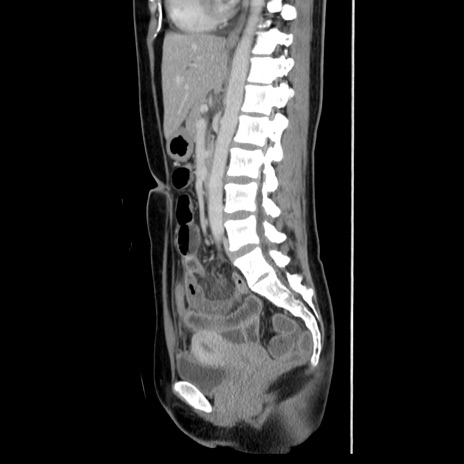

症例39(矢状断像)

【症例】40歳代女性

【主訴】上下腹部痛

【現病歴】2日目から下腹部痛あり。夜間は痛みで眠れなかった。昨日より上腹部痛と下痢が出現。臥位で痛みは軽快したため、休んでいた。本日になって臥位でも立位でも痛みが強くなってきたため救急要請。

【既往歴】子宮内膜症

【身体所見】部:平坦・軟、左上下腹部に圧痛あり、反跳痛あり。

【データ】WBC 21800、CRP 26.78

CT